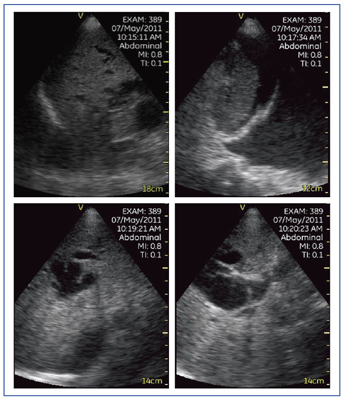

図7は,原発性肝細胞がん破裂例である。Vscanでは,浅部の描出をやや苦手としているため,本症例においても図7 aでは腹水内の血液が点状エコーとして描出されていない。しかし,視野の中心に対象が来るようにプローブを走査し,プローブと腹水の間の距離を十分に保つことで,より細かい観察が可能となる(図7 b)。

図7 症例2:原発性肝細胞がん破裂